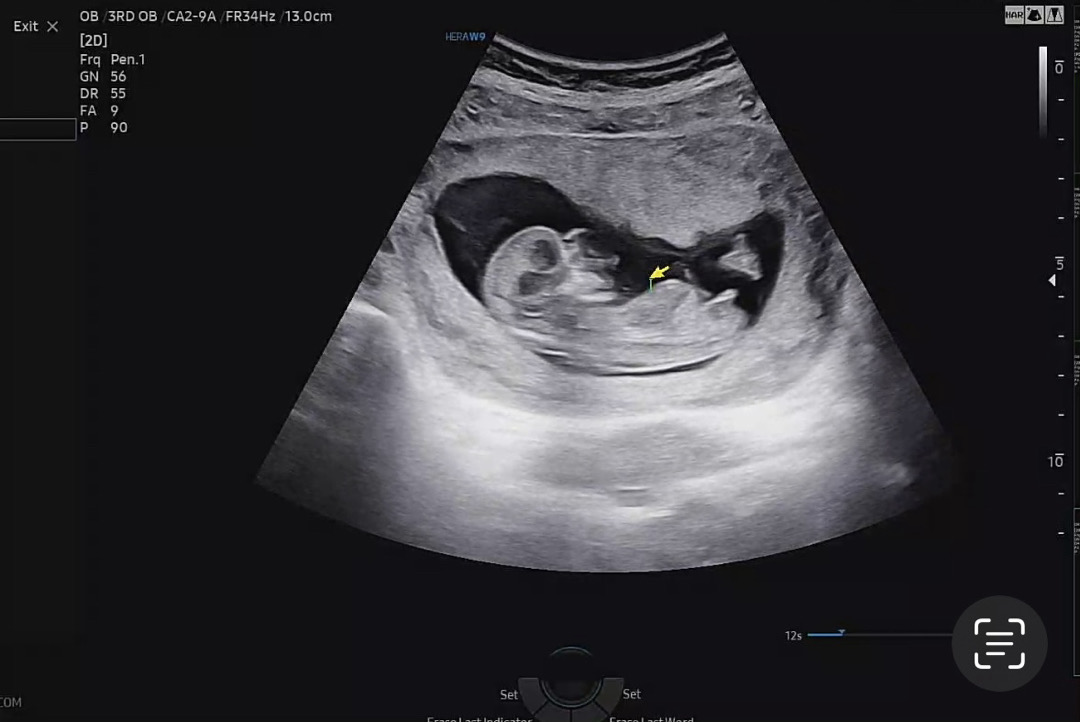

12주 1일 각도법 참견부탁드려요!

문제가 되면 삭제하겠습니다. 투표해주신 분들 감사드려요🙏🏻